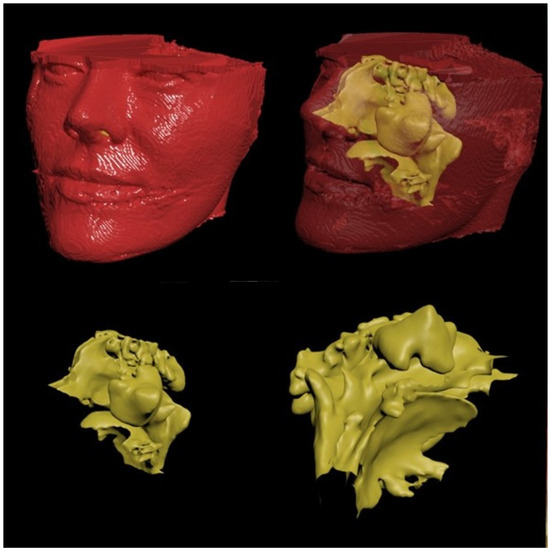

2.1. Digital Modeling

- Generation of the geometric model for CFD numerical analysis from the CBCT image.